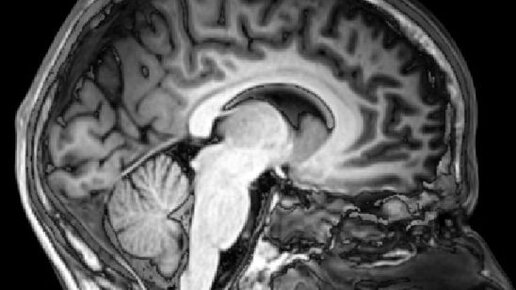

МРТ головного мозга - это неинвазивный способ диагностики, который выполняется при наличии как хронических, так и острых симптомов заболеваний головного мозга. Процедура сканирования производится при помощи...

Многие люди до сих пор боятся МРТ, но в некоторых случаях это единственный метод, который может подтвердить или опровергнуть серьезные опасения врачей. Особенно когда дело касается нарушений работы головного мозга...